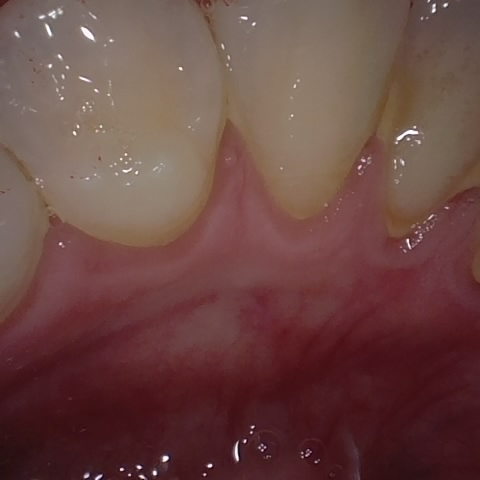

Annotated as "Good"